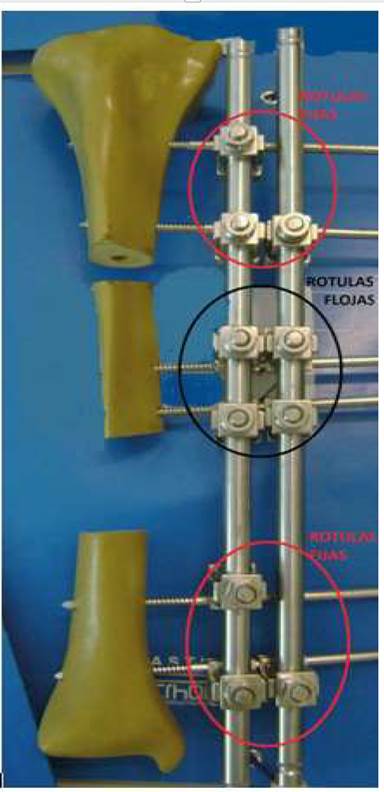

Ilizarov en Siberia, en 19513)(4, diseñó un sistema de fijación versátil, económico y con un gran número de aplicaciones en la resolución de patologías osteoarticulares traumáticas, infecciosas, congénitas y tumorales, el cual continúa vigente en la actualidad.

El método de transporte óseo se basa en un principio fundamental que es la inducción de la osteogénesis en distracción de fragmentos óseos, lo que busca la formación de tejido óseo de excelente calidad biológica, donde traslada un segmento de hueso en dirección longitudinal, bajo los principios de tensión-estrés, permitiendo dicho procedimiento1)(3)(4)(5)(6)(7)(8.

3) Osteotomía proximal o distal de tibia metafisaria según localización del defecto óseo en diferente incisión quirúrgica, la misma se puede realizar con escoplo, sierra Gigli o con mecha. Osteotomía de peroné.

4) Revisión del montaje y alineación del miembro, revisión de osteotomía.

5) Período de latencia de 10 días con compresión del foco de osteotomía.

7) A los 10 días distracción a una frecuencia de 1/6 rosca cada 4 horas.